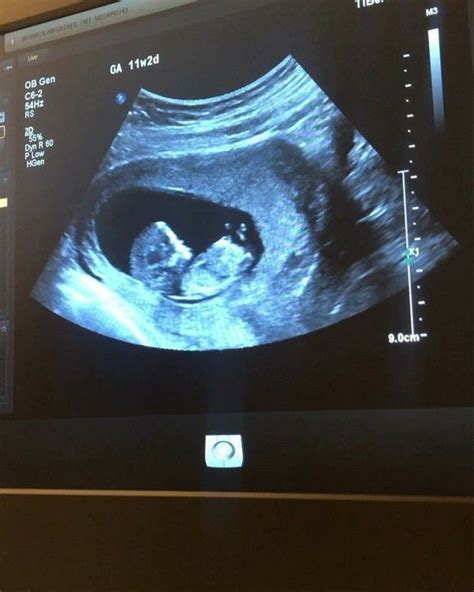

Jeigu echoskopijos metu matosi, kad vaisius labai spurda ir juda, ar tai gerai? Nėra mokslinių tyrimų, kurie akivaizdžiai teigtų apie ultragarso bangų žalingą poveikį vaisiui. Tačiau žinoma, kad jos sukuria šilumą, todėl laikant daviklį vienoje vietoje ilgiau - gali pradėti šilti ir vaisiaus vandenys. Vis dėlto, rekomenduojama nepiktnaudžiauti ir atlikti tik būtinąsias ultragarsines patikras (Lietuvoje rekomenduojama 11-14 ir 18-21 nėštumo savaitę). Ypač nerekomenduojama pramoginiais tikslais atliekama 3D/4D ultragarsinė apžiūra.

- 11 savaitė: Būsimas naujagimis yra figos dydžio. Neįtikėtina, bet nuo šios savaitės iki gimimo jo svoris paaugs apie 30 kartų, o ūgis padidės triskart. Kūdikio ūgis: apie 40 mm. Svoris apie 7 gr.